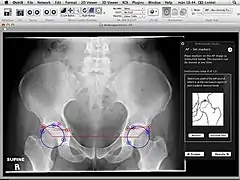

Orthopaedic Studio is an application designed to help orthopaedic specialists perform several common quantitative hip examinations that are based on standard x-ray images.

The application is implemented as a plugin for the medical image viewer OsiriX and thereby only runs on Mac OS X.

Orthopaedic Studio evaluates four different types of hip radiographs (standing anteroposterior, Von Rosen, false profile and frog). On such images a number of standardized angles, offsets and ratios can be measured, including:[1]

• Lateral collateral ligament angle

• Tönnis angle

• Joint space width

• Pelvic tilt and rotation

• Anterior centre edge angle

• Femoral head-neck offset ratio

• Frog Alpha angle

• Frog modified Alpha angle for slipped capital femoral epiphysis (SCFE)

• Epiphysis-metaphyseal offset for SCFE

• Southwick angle for SCFE